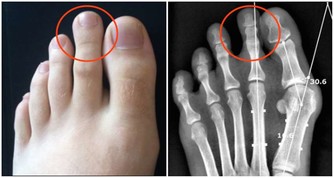

腳是離心臟最遠的部位,不容易得到養分與血液。

睡前用溫熱的水泡一泡腳,對促進身體血液循環、加速新陳代謝都有好處。

泡腳的黃金時間點在9點左右,在此時泡腳,能讓腎臟得到最大程度的放鬆。